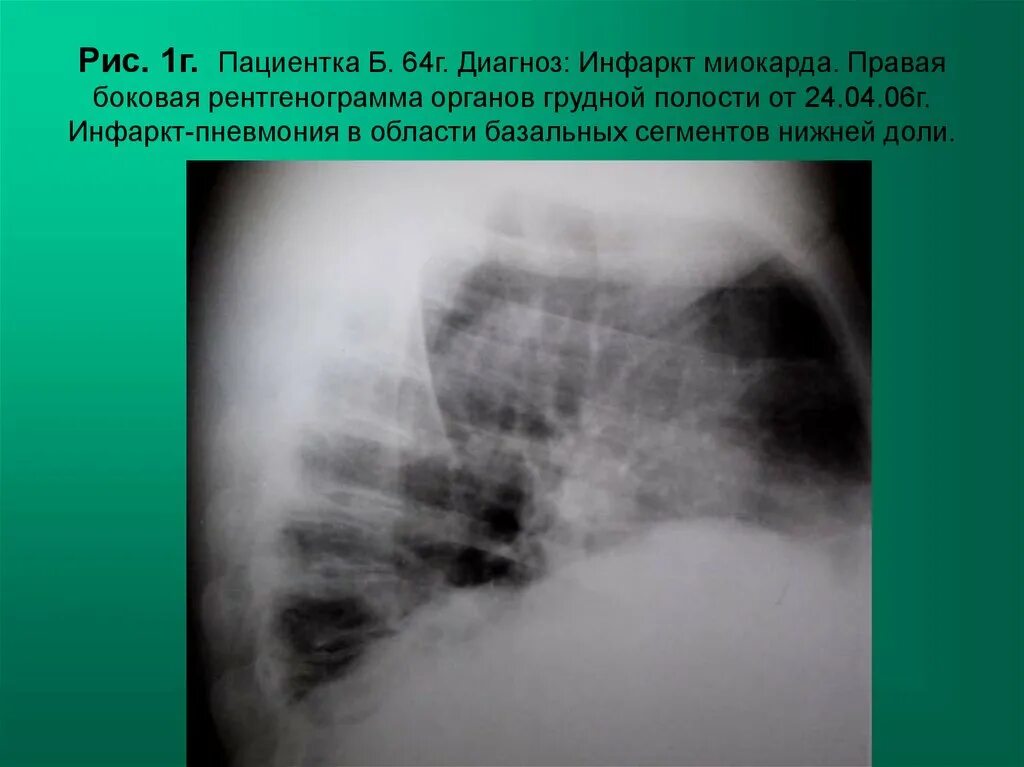

Диагноз г 80